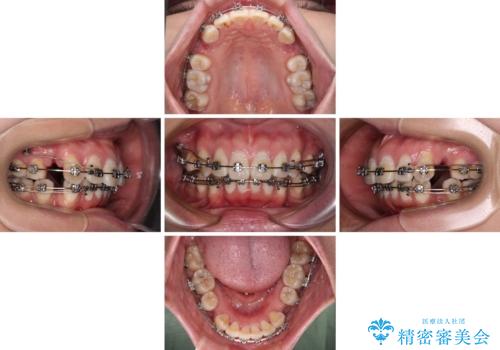

- メタルブラケット

- 2年6ヶ月

骨格的に上顎歯列が前方位にあり、口元の突出感が顕著な状態で、上下左右の第一小臼歯4本を抜歯して、ワイヤー装置での抜歯矯正を行うこととしました。

奥歯の咬み合わせ改善のために、アンカースクリューの使用と上顎左右第一小臼歯の抜歯のタイミングをコントロールして、理想的な咬み合わせに仕上げていくこととしました。

ご本人がびっくりするくらい劇的に口元の突出感が改善され、大変満足のいく仕上がりとなりました。